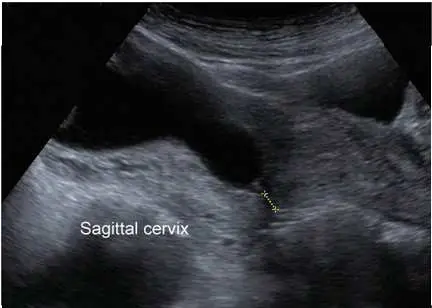

一位 31歲懷孕22 週 G2P1 的孕婦,來產檢時超音波檢查發現如附圖。她前一胎於懷孕 33週時自發性早產(spontaneous preterm),依她目前的狀況,下列何者是最適合的處置?

從附圖可見經陰道超音波(sagittal view)所量測之子宮頸,由內口(internal os)至外口(external os)間距明顯縮短,並以游標標示此距離。讀片者可估算該長度約在15–20 mm之間(正常應為30–50 mm),顯示「短頸管」現象,此改變已足以提示極高的自發性早產風險。